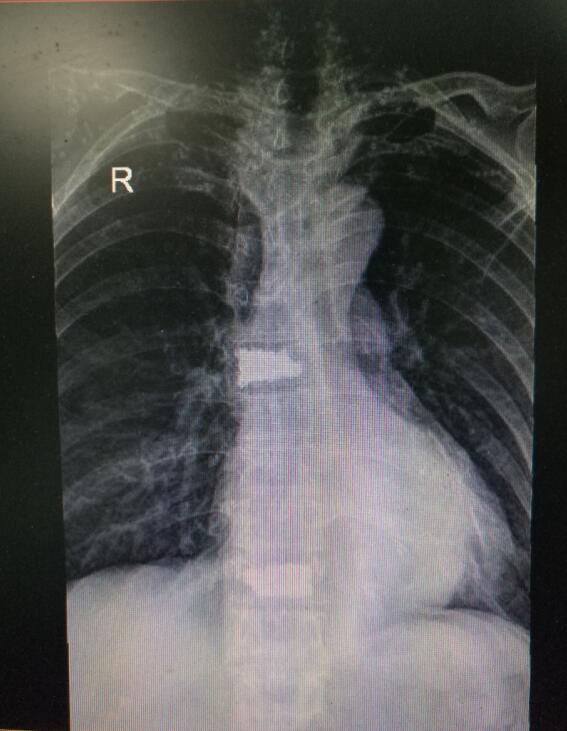

術(shù)前DR(數(shù)字化的x射線)